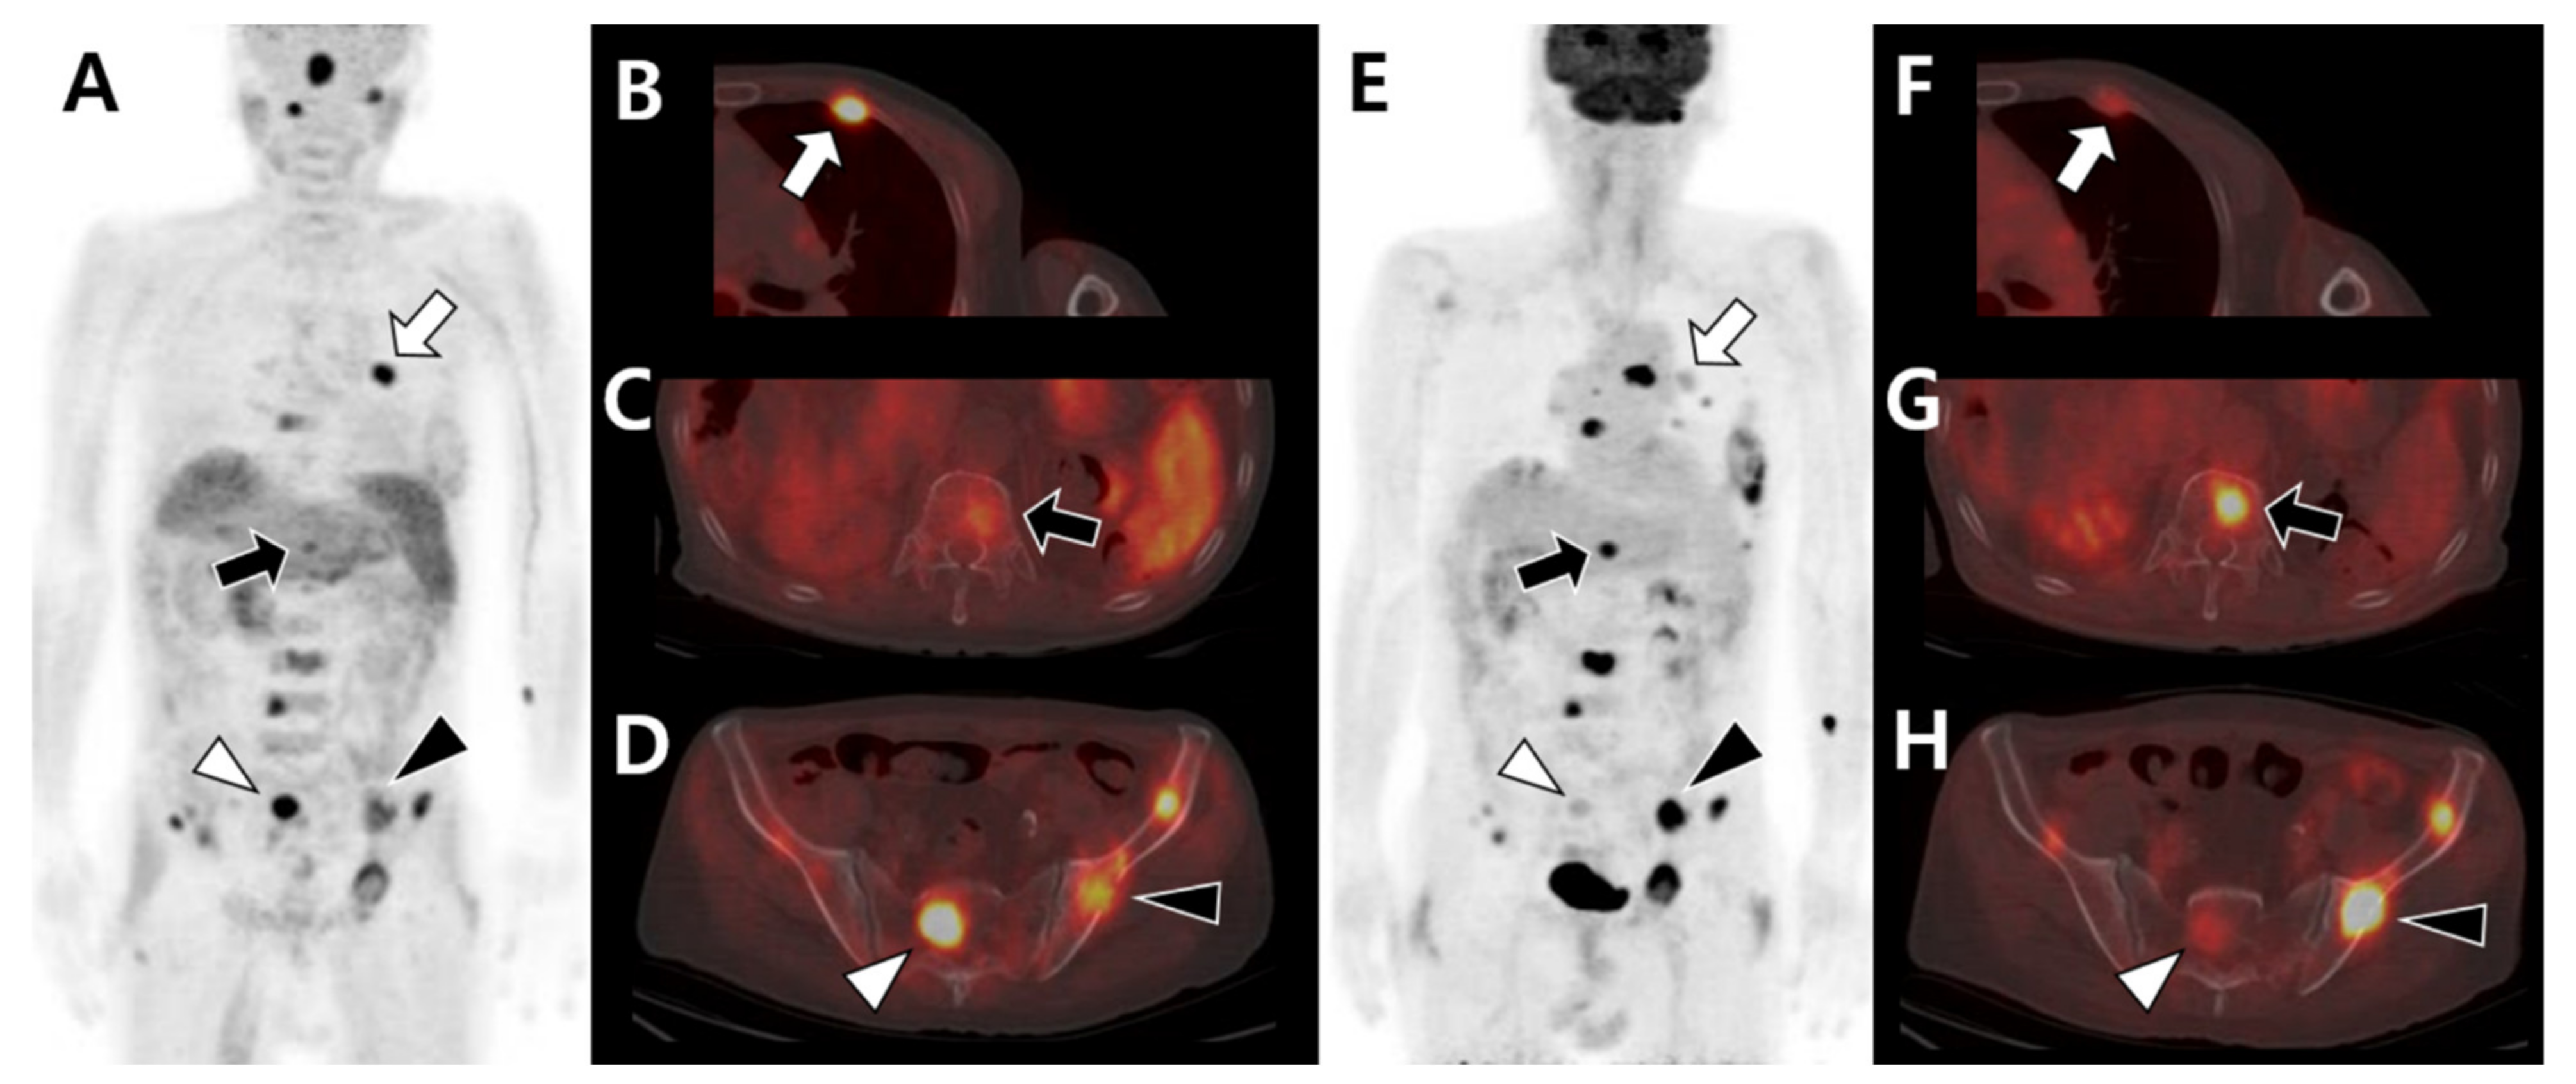

3.2. Multimodal Imaging According to the Differentiation Status of the Primary Tumor

4. Imaging Patterns Based on the Bone Microenvironment